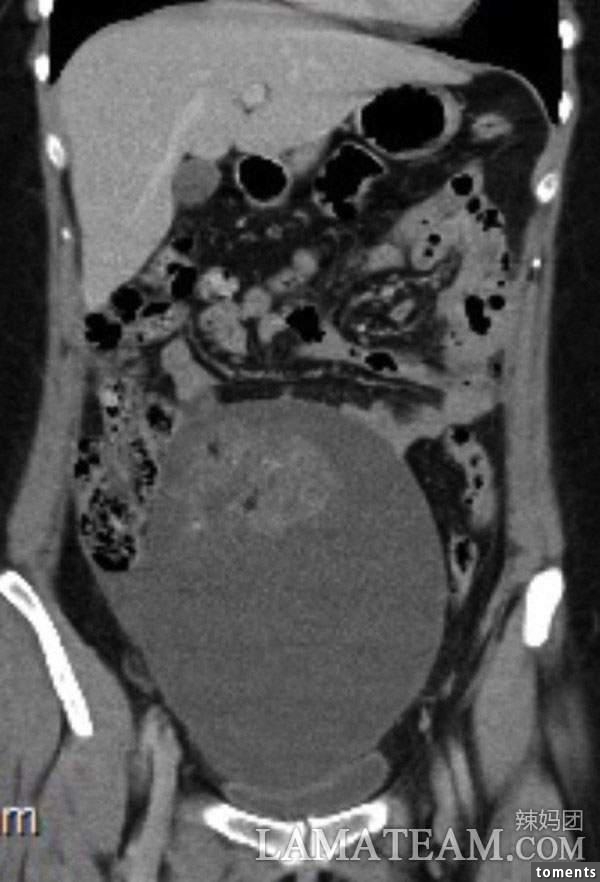

最後醫生做了活組織切片,結果表明路易斯患了未成熟卵巢畸胎瘤。

從片子中可以清楚看到這個腫瘤已經佔據她的整個胃部,還在壓迫著其他器官。

這種情況只能手術,醫生先把腫瘤壓縮,到了可以移除的大小進行切除,然後修復卵巢和輸卵管,就這樣進行4個小時的手術一切順利,而且還不會影響路易斯以後的生育。